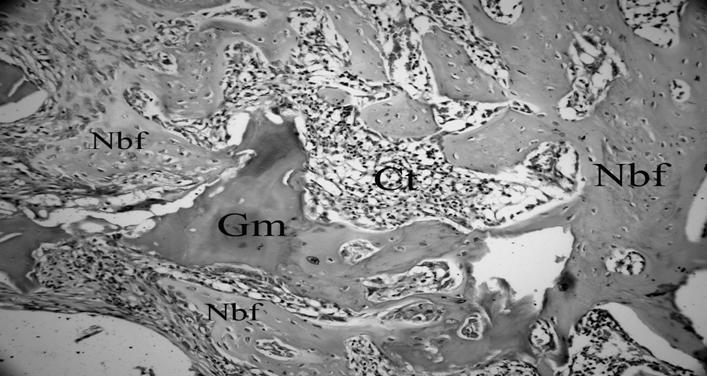

Figure 3

CPCBB graft material which is gradually resorbing and resembles the necrotic bone can be seen in the middle of this slide. This section has been taken from the CPCBB + HBOT group which was sacrified at four week time point (H&E×200) (Nbf; New bone formation, Gm; Graft material, Ct; Connective tissue).

In groups which received HBOT, overall bone healing pattern was similar to non-HBO groups. However, from a subjective point of view, new bone formation was occupying larger areas which were previously filled by cartilage and fibrous connective tissues in groups which did not receive HBOT. At one week, there was no prominent inflammatory cell reaction in any of the three groups. Loose connective tissue and new bone trabeculae were found together with small islands of isolated cartilage tissue and abundant new vessels in the control group and around the bone grafts (Figure 1b, 1c). At two weeks, no cartilage or necrotic tissue formation was observed in the control group. Moreover, most of defects were already filled with newly formed bone. Similar observations were made in the groups in which the bone grafts and HBOT were used together. There were also prominent new vessel formations within the connective tissue surrounding the graft particles (Figure 1d). At four weeks, nearly all of the fibrous tissue was replaced by the newly formed bone in the control group. In β - TCP + HBOT group, there was some areas of residual graft particles surrounded mainly by a combination of mature and immature bone. Smaller areas containing graft particles were also present in CPCBB + HBOT group, however, the healing of defects in this group were close to that of the control group (Figure 2, 3 and 4).